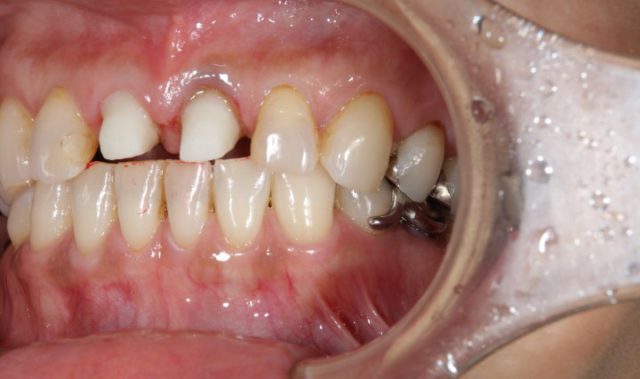

施術中

施術中です。オールセラミックをかぶせるための土台を形成しています。